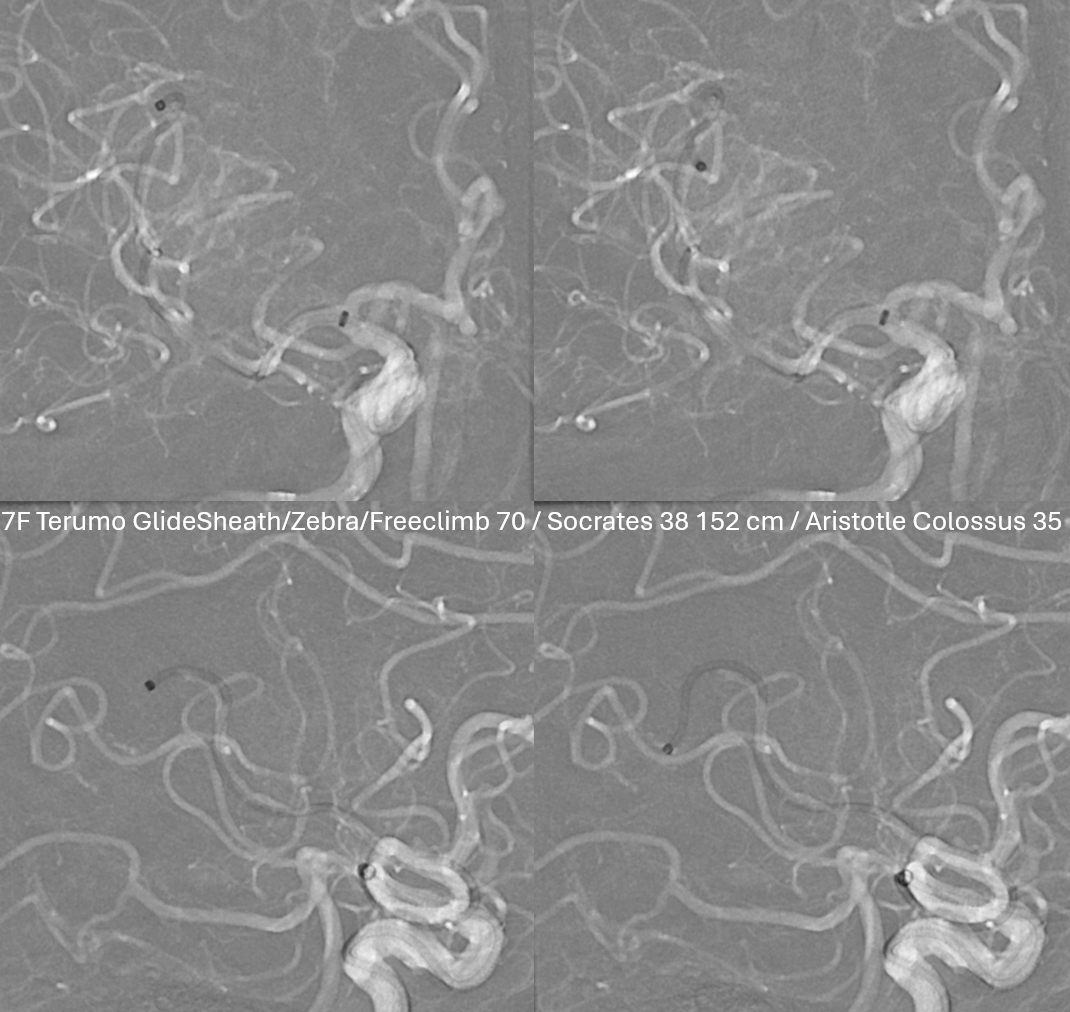

Lets do a dry DYNA. 20 sec 70 kEv spin, 35 cm FOV, noncontrast. Takes 3 minutes to do, including setup, acquisition, and analysis

Not much to see on source data

Reconstruction, original. See the two separate hyperdense areas?

This is definitely good enough. A secondary reconstruction in “normal” or “sharp” modes can make it a bit better, but not necessary

Now lets make a 3-5 mm thick MIP to see it better. We are looking at two occlusions. Each occlusion is at the distal end of the associated hyperdensity — where the contrast column stops (arrow – M2, dashed arrow — distal M2). Retrospectively one can see the distal occlusion on CTA, but not on catheter angio. Here we can definitively say that this is a tandem lesion, not a distal embolus after the upcoming proximal M2 aspiration.